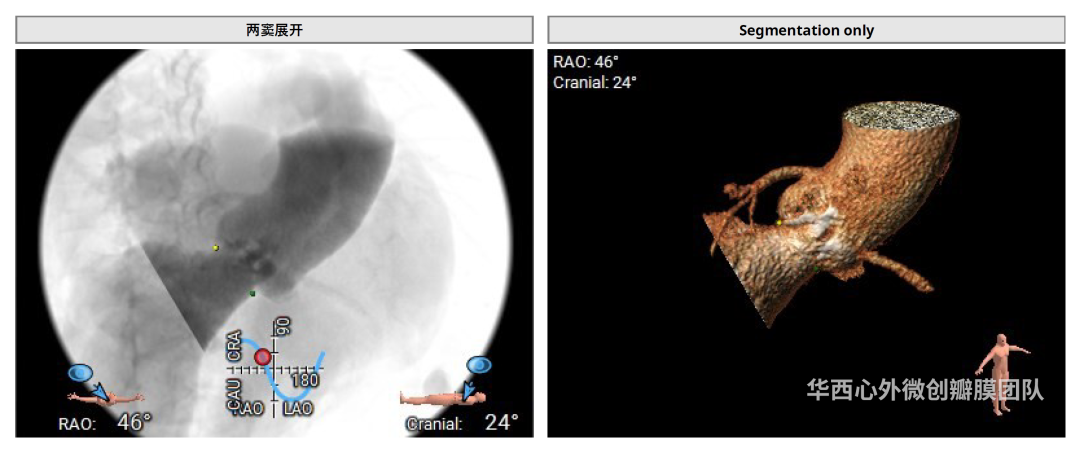

术前CT评估

患者镜面右位心,主动脉瓣二叶式,Type 0-lat型,瓣环面积410.3mm²,面积折算直径22.9mm,左冠开口高度14.1mm,右冠开口高度14.7mm,瓣叶增厚,重度钙化,主要分布于瓣叶游离缘,瓣环、流出道、STJ未见明显钙化累及,升主动脉可见扩张,近横位心58°。患者外周血管条件尚可,胸主动脉迂曲、成角90°,未见明显钙化。